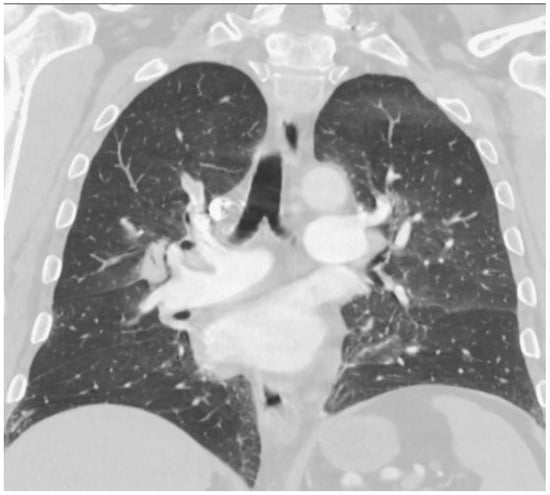

2. Case Report